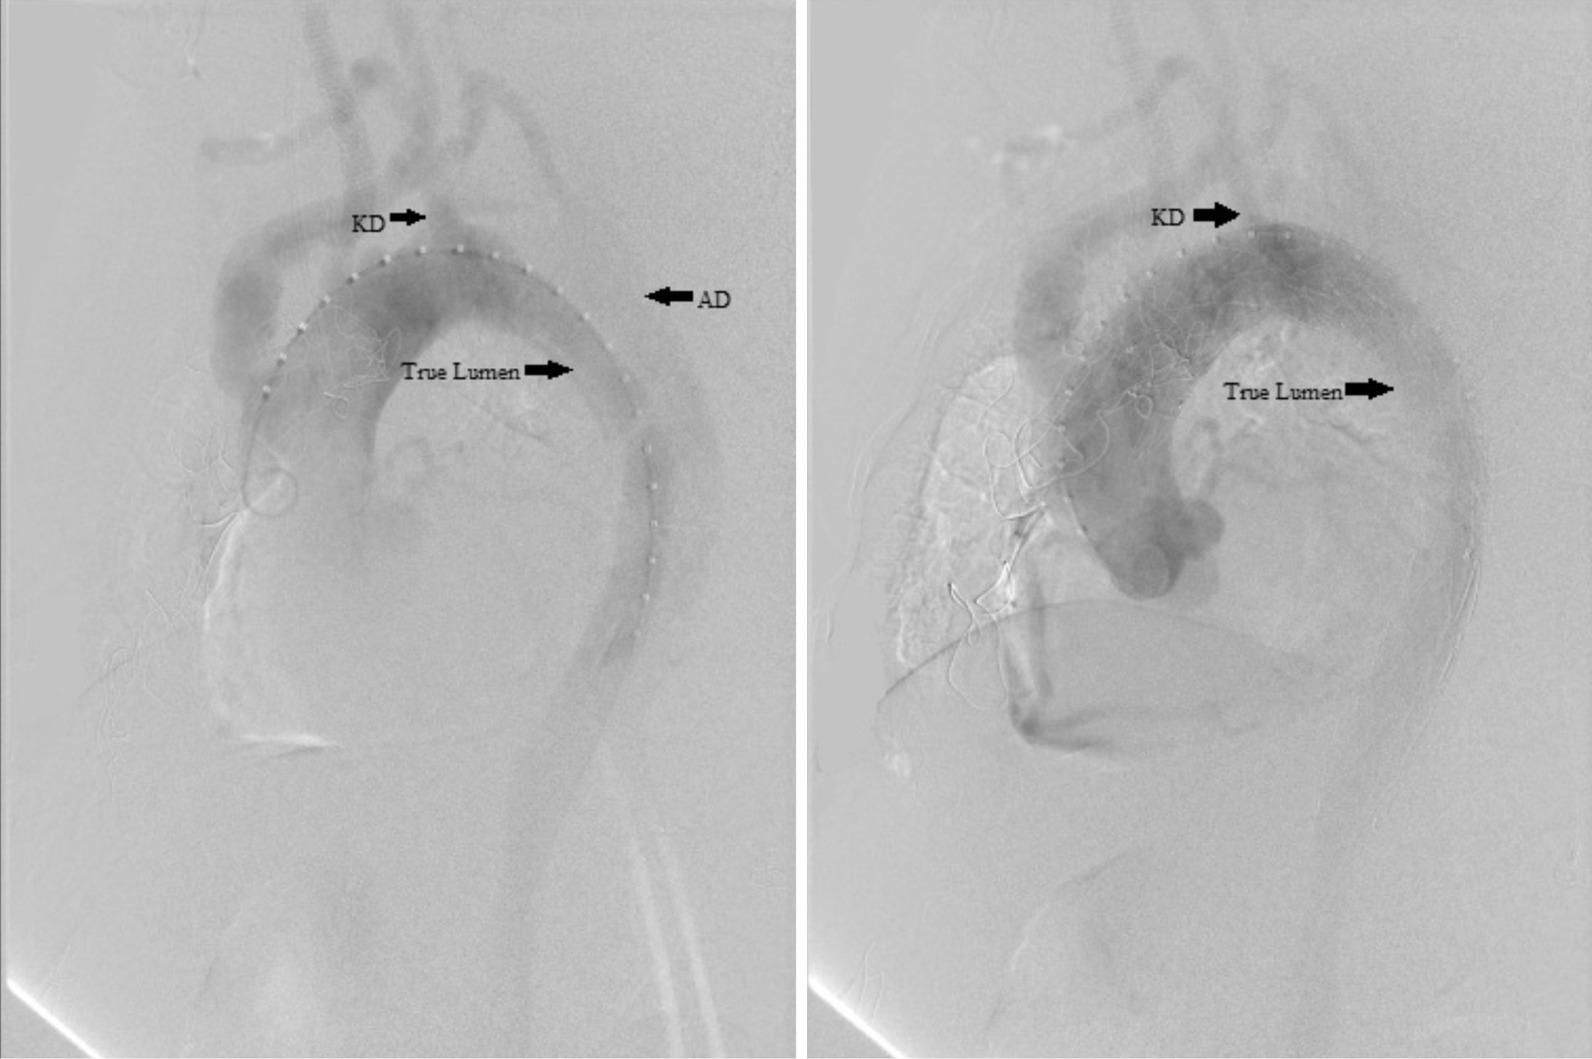

A case of successful hybrid repair of distal aortic arch dissection aneurysm by dissecting KD and ARSA with debranching of right and left common carotid arteries, left subclavian artery, and stent grafting was presented.

本文报告了一例成功的杂交手术修复降主动脉夹层动脉瘤的病例,该手术通过对 KD 和 ARSA 进行解剖,并对右颈总动脉、左颈总动脉、左锁骨下动脉进行分支重建,同时进行支架移植。